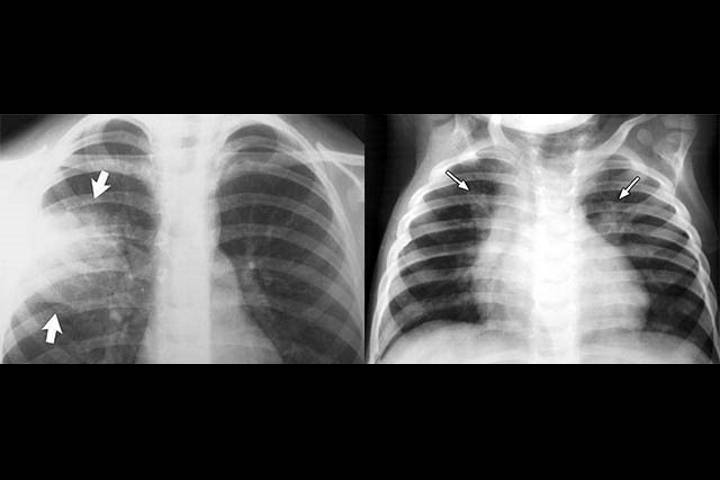

Признаки и симптомы больничной пневмонии у пожилых и старых людей

Для «типичной» формы характерно резкое повышение температуры, которое сопровождается кашлем и обильными гнойными выделениями. В некоторых случаях отмечается плевральная боль. Во время диагностического исследования зачастую выявляют такие отклонения как: жесткое дыхание, хрипы, затемнения на рентгенологических снимках.

- изменения на снимках с рентгена.

- рентген-исследования;